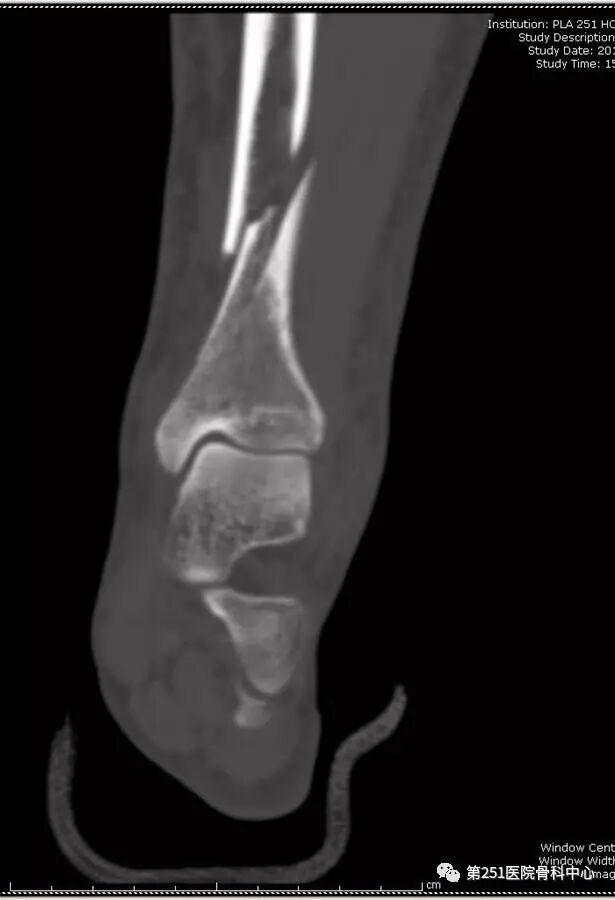

病例6:男性,39岁,车祸伤SchatzkerⅥ型胫骨平台骨折。

![]()